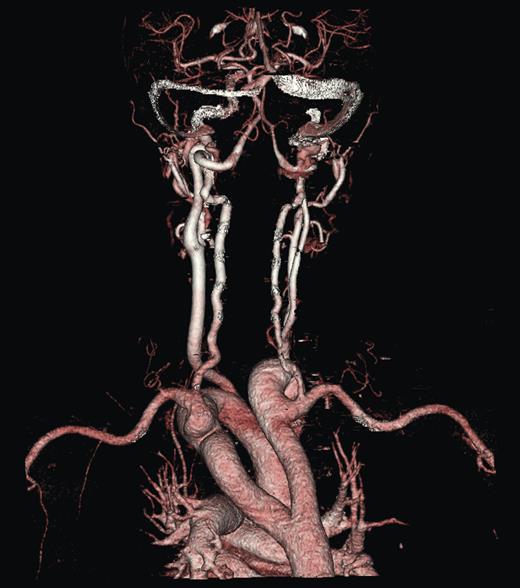

A duplex scan performed on this presentation demonstrated a high, prominent and ectatic aortic arch visible above the sternum, with a diameter of 2.0 cm. The innominate artery appeared ectatic, tortuous with localized wall thickening and had a reported diameter of 1.8 cm. An outpatient computed tomography (CT) angiogram was arranged to help delineate the underlying anatomy. Figure 3 shows a coronal section of this CT angiogram. Figures 4 and 5 show the anterior and posterior views of the 3D reconstruction, respectively.

Figures 3–5 demonstrate a DAA with the right carotid and right subclavian arteries arising from the right-sided arch and left carotid and left subclavian arteries from the left-sided arch. There is also a minor narrowing of the right-sided arch at a kink between the right carotid and subclavian origins. Figure 3 demonstrates both arches rising up into the neck explaining the clinical presentation.